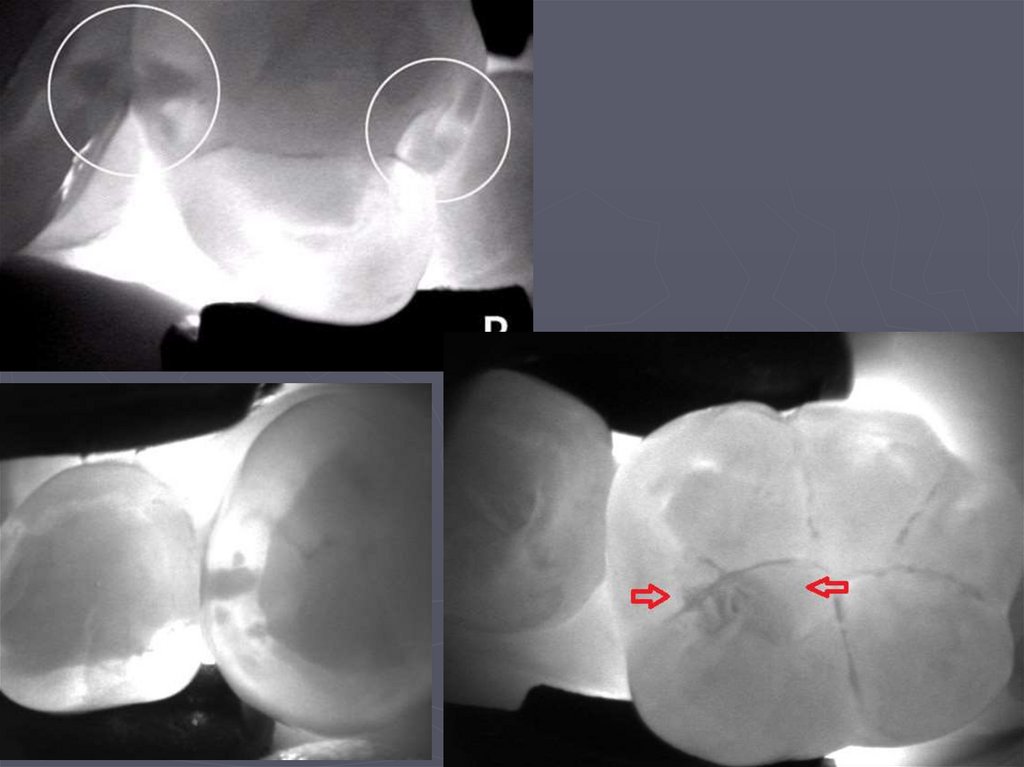

DIAGNOCAM CAVO